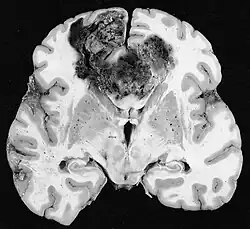

Glioblastome

Les tumeurs des cellules gliales les plus courantes et les plus malignes sont les glioblastomes. Ils consistent en une masse hétérogène de cellules d'astrocytome peu différenciées principalement chez l'adulte. Ils surviennent généralement dans les hémisphères cérébraux, plus rarement dans le tronc cérébral ou la moelle épinière. Sauf dans de très rares cas, comme toutes les tumeurs cérébrales, elles ne s'étendent pas au-delà des structures du système nerveux central.

Le glioblastome peut provenir d'une forme diffuse (II. grade) ou un astrocytome anaplasique (III. grade) développer. Dans ce dernier cas, il est dit secondaire. Cependant, lorsqu'elle survient sans antécédent ni signe de malignité antérieure, on parle de maladie primaire. Les glioblastomes sont traités par chirurgie, radiothérapie et chimiothérapie. Ils sont difficiles à guérir et rares sont les cas qui survivent au-delà de trois ans.